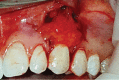

Gingival recession is an oral health problem that affects a large part of the population. Several treatments are suggested in the current literature; among them is the use of buccal fat pad grafting. The objective of this case report is to describe the treatment of a Miller Class I gingival recession using a nonpedicled buccal fat pad graft immediately after performing the surgery for buccal fat pad removal (bichectomy technique). First, bilateral surgical removal of the buccal fat pad was performed with the main objective of eliminating oral mucosa biting. The recipient site was prepared to receive a portion of the fat pad that was cut and macerated in a size that was sufficient to cover the recession. The patient was followed up at 15, 30, 60, and 365 days postsurgery, and the results showed an elimination of the oral mucosa biting and complete coverage of the gingival recession. It was concluded that the nonpedicled buccal fat pad graft is another option for the treatment of Miller Class I recessions.